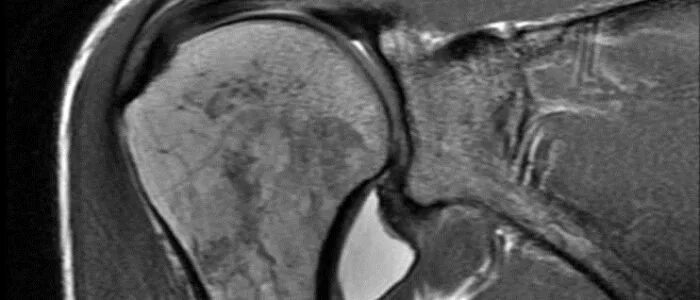

Мрт при боли в суставах